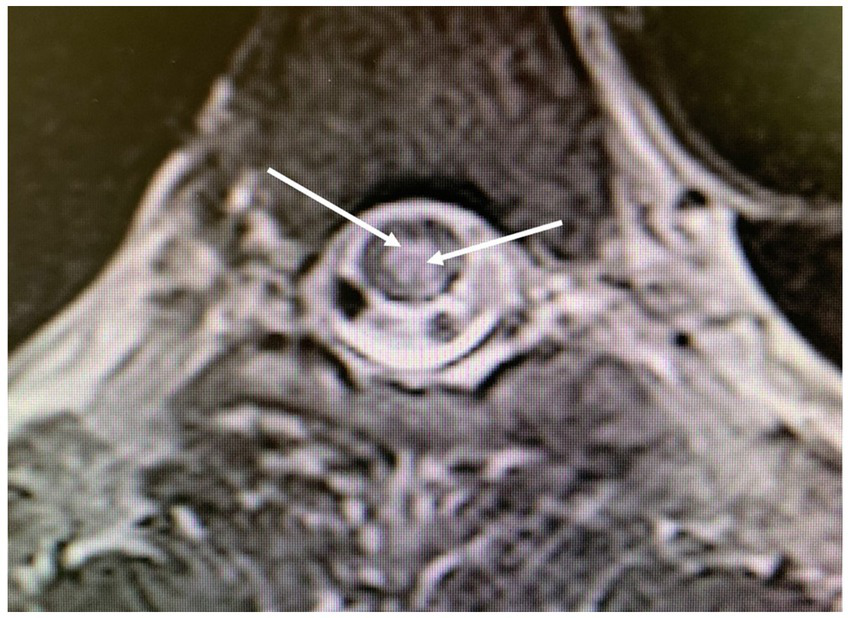

Figure 4

Magnetic resonance imaging of the thoracolumbar spinal cord; axial T2-weighted images obtained 5 days after the second diving incident display abnormalities in spinal cord signal intensity (indicated by arrows), with involvement of the posterior medulla and gray matter.

Five days after the second incident, a medullary MRI was performed, which revealed a T2-weighted hypersignal extending intramedullary from level T2 to T8 in sagittal sections (see Figure 3). This hypersignal affected both the posterior cords and the gray matter in the axial section (Figure 4).

Another aspect for discussion pertains to the region of spinal cord injury identified during the MRI conducted after the second incident. Literature data from several years ago (7, 9) indicate that MRI findings in cases of Spinal cord DCS more commonly reveal ischemic lesions in the posterior or lateral columns of the spinal white matter, with central gray matter involvement being less prevalent. Nevertheless, gray matter involvement can also manifest in certain severe cases of Spinal cord DCS (15), as observed in the case we present (Figures 3, 4). We attribute this observation to advancements in imaging techniques with newer generations of MRI, facilitating a more precise analysis of spinal cord lesions, including the more frequent detection of gray matter involvement in Spinal cord DCS cases compared to previous methodologies.